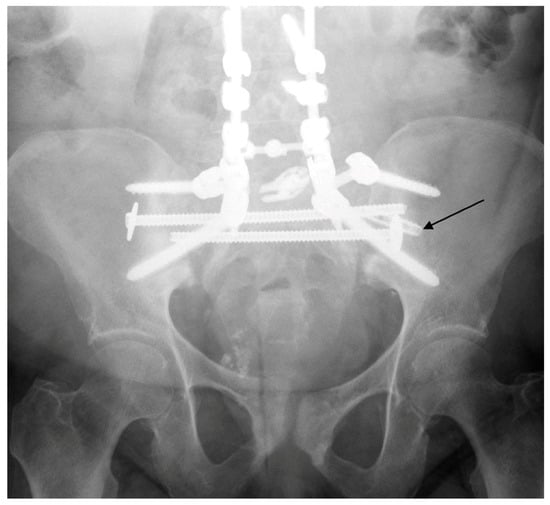

6. Spinopelvic Fixation Percutaneous Technique

7. Tran-Sacral Percutaneous Technique